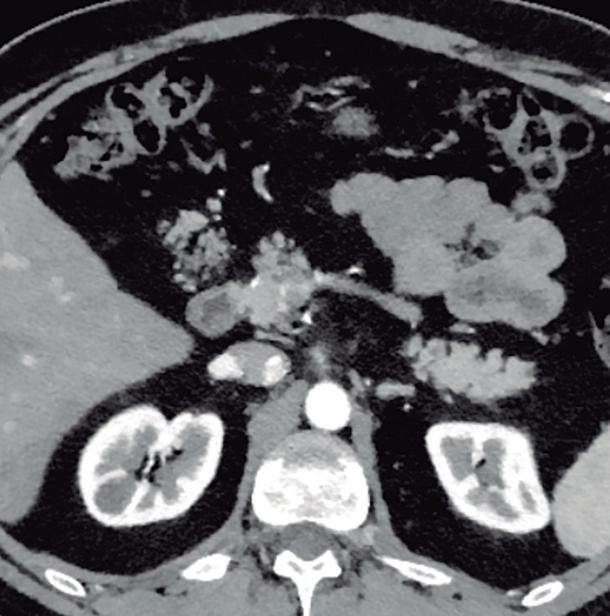

Páncreas Anular

Consiste en una anomalía de la migración del brote pancreático ventral, el cual no rota o lo hace de manera incompleta, resultando en la presencia de tejido glandular pancreático a la derecha del duodeno, rodeando a su 2° porción (Figura 8). Han sido descriptos dos subtipos: el extramural, donde el conducto de Wirsung rodea al duodeno uniéndose al conducto pancreático principal; y el intramural, donde el tejido pancreático se entremezcla con la pared duodenal y sus secreciones drenan directamente a la luz a través de conductos muy pequeños.16

En las imágenes encontramos parénquima pancreático rodeando a la 2° porción duodenal, habitualmente en toda su circunferencia y en ocasiones de manera incompleta. En la colangio-RM es posible visualizar al conducto pancreático a la derecha del duodeno, con un recorrido que se dirige a la ubicación de la papila mayor (Figura 9).17

Más allá del diagnóstico de esta anomalía debemos buscar signos imagenológicos indirectos de obstrucción gastrointestinal, como son la dilatación gástrica y de la 1° porción duodenal (Figura 10), con estrechez de la luz del duodeno en el sitio por donde transcurre a través del páncreas anular.18,19

A) Tomografía computada con contraste, plano coronal. El páncreas anular (flecha) provoca dilatación de la 1° porción del duodeno (cabezas de flecha). B) Tomografía computada con contraste, plano axial. Flechas: páncreas anular. Cabeza de flecha: duodeno. C) Tomografía computada con contraste, plano axial, corte más caudal que el previo. Flechas: páncreas anular.

Figura 10. Páncreas anular con obstrucción del tracto de salida gastrointestinal